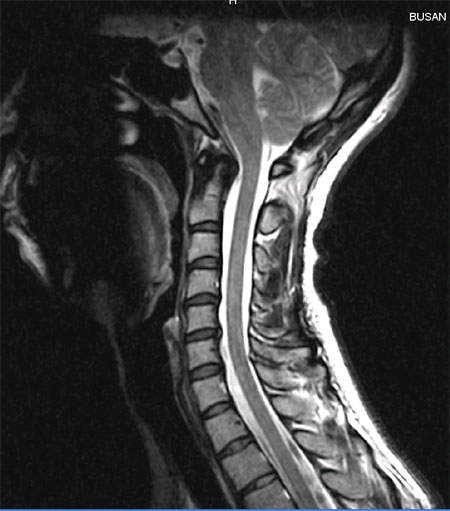

(ֹȣ : 26c606c15be6 / ī,ͳݹŷ ιȣ : 62602800) , ü Ư Ű 162 Cm ü 53 Kg 35 --------------- ȣϽ ---------------------- ȯ 1C.Ż, 1C.ڵ, 1C.ھ, 1C.̸, 1C.ڱӼ , 2C.ھȱ , 2C.ھȱ, 4C.û°, 6C.ڸ , 6C.ھ Ḳ , 6C.ڻ , 7C.Ȳġ, 1T.ڼո , 1L., 3L.ڹ ().ڲ ()ũ( ߰Ż), ũ(߰Ż), ũ(߰Ż)ġ, , Ḳ , , Ḳ ġ Ϳ︲, ̸, Ϳ Ҹ , ȯû Ǵ ġ ͳ ˻ڷ õ 1. ΰ 2006 10ʿ ġԴϴ 2. ũ 2007 9 mri ôµ 5-6 Դٰ մϴ ɰ ´ ƴ϶ ϰ Ŵϴ 3. 㸮 ֽϴ |